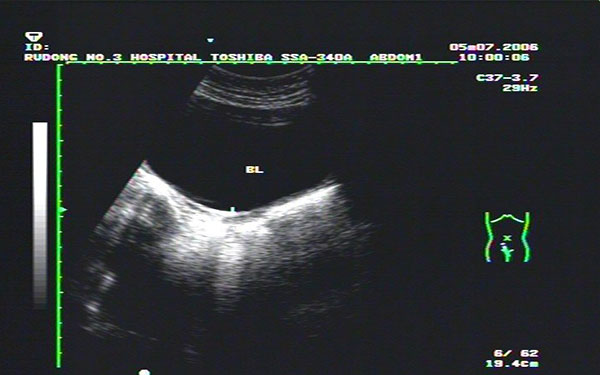

始基子宫的诊断可依靠电子阴道镜,腔内四维彩超,染色体分析和电化学发光法内分泌检测就可确诊。其超声诊断表现为:

1. 盆腔内膀胱后方可见实性肌性似子宫样回声,子宫非常小似一条索状,纵径小于2cm,前后径小于1cm,无宫腔线和内膜回声;

2. 始基子宫为双侧副中肾管融合不久即停止发育,子宫极小,多数无宫腔或为一个实性肌性子宫,偶可见始基子宫有宫腔和内膜;